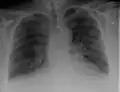

Chest radiograph of a lung with distinct Kerley B lines, as well as an enlarged heart (as shown by an increased cardiothoracic ratio, cephalization of pulmonary veins, and minor pleural effusion as seen for example in the right horizontal fissure. Yet, no obvious lung edema is seen. Overall, this indicates intermediate severity (stage II) heart failure.

Chest X-rays are frequently used to aid in the diagnosis of CHF. In a person who is compensated, this may show cardiomegaly (visible enlargement of the heart), quantified as the cardiothoracic ratio (proportion of the heart size to the chest). In left ventricular failure, evidence may exist of vascular redistribution (upper lobe blood diversion or cephalization), Kerley lines, cuffing of the areas around the bronchi, and interstitial edema. Ultrasound of the lung may also detect Kerley lines.[73]